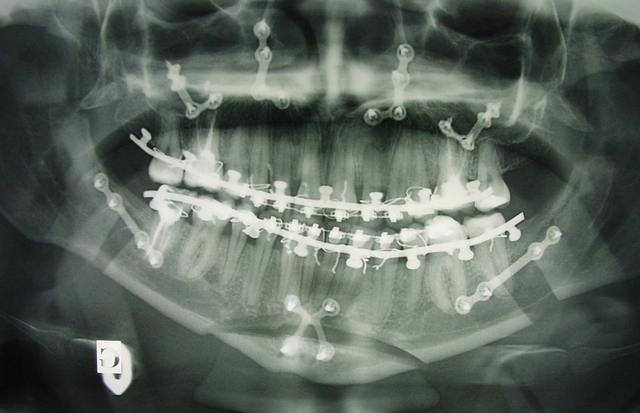

chir d'avancée mand et max

voici les radios de ma chir, j'aurais les photos lundi pour ceux que ça intéresse.

pour manger, régime sec les 4 premiers jours (4kg en moins cOol) puis à la cuillère parce que la paille pas terrible.

aujourd'hui 1 mois après je mange du riz, des pâtes, du poisson, steak haché, des trucs qui se broient facilement sinon j'ai trop mal aux atm.

les nerfs repoussent et j'ai encore bien mal par moment, j'ai arrêté la lamaline (3 semaines mais complètement choutée) et je suis juste au paracetamol.

mes motivations : craquements atm, douleurs, petite ouverture buccale (pas toujours pratique pour manger => je ne parle pas de ce à quoi les hommes vont penser mais à un gros big mac ;))) )

et bien sur en prévention pour les années à venir.